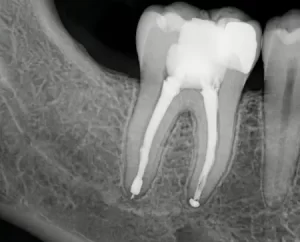

Корневой канал — это полость, где располагается пульпа, состоящая из пучка нервных окончаний, кровеносных и лимфатических капилляров, «питающих» зуб. По сути, это вся внутренняя часть зуба, которая скрывается за слоем дентина и прочной эмали. Но если кариес глубоко проникает в зуб, то корневой канал инфицируется. Туда может попасть инфекция, мгновенно провоцирующая воспалительный процесс: это своего рода защитная реакция организма. Вместе с этим там может образовываться гной, и если своевременно всё это не убрать, то можно потерять зуб.

Длительная зубная боль (которая не проходит в течение дня) — тоже является явным признаком, что требуется лечение у эндодонта. Однако масштаб проблемы можно будет определить только на основании осмотра или вскрытия кариозной полости. Дополнительно врач может направить на рентгенологическое обследование.

- Рентгенологическое обследование.

Также в нашей стоматологической клинике в Минске практикуется лечение корневых каналов под микроскопом. Это — инновационная технология оказания помощи. Она позволяет максимально детально оценить состояние пульпы, и самое главное — не оставить кариозных частей. При лечении под микроскопом вероятность возникновения осложнений практически полностью исключена.